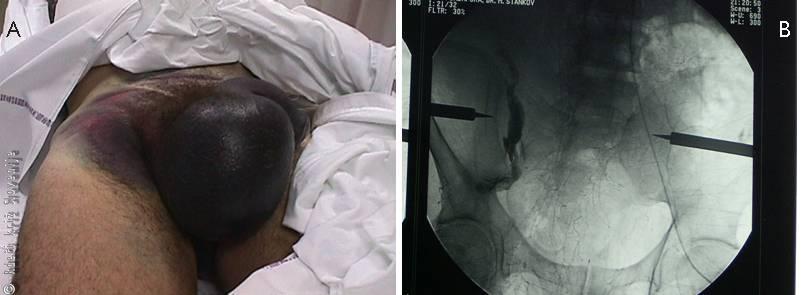

Slika 3

A – Podplutbe v predelu genitalij in perineja.

B – Angiografija, ki kaže iztekanje kontrasta iz arterij v poškodovani medenici, kar kaže na krvavitev.